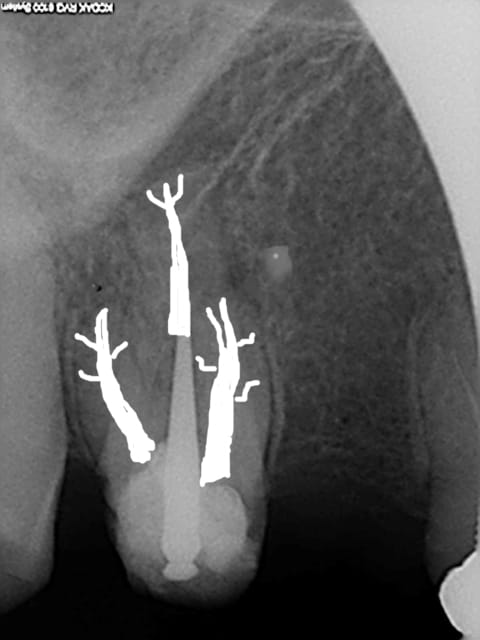

Pas mal photo shop. mais j'ai des progrès à faire. Superbe endo en tout cas vive la vague de gutta chaude. )))))))

R1 modifie  1 mextcw - Eugenol

P2eqdh3csim6s7nb09ktdq3e7ev8 - Eugenol

Un peu trop blanc mais ça simplifie la sélection après. Une fois re sélectionné, il suffit de modifier la teinte pour un peu plus de grisé.

C'est un nouveau matériau d'obturation, hyper dense !))))je me suis servi de la gomme. C'est le bordel pour choisir les couleurs.

Celle là est mieux, Comment fait on pour changer les couleurs du crayon ?